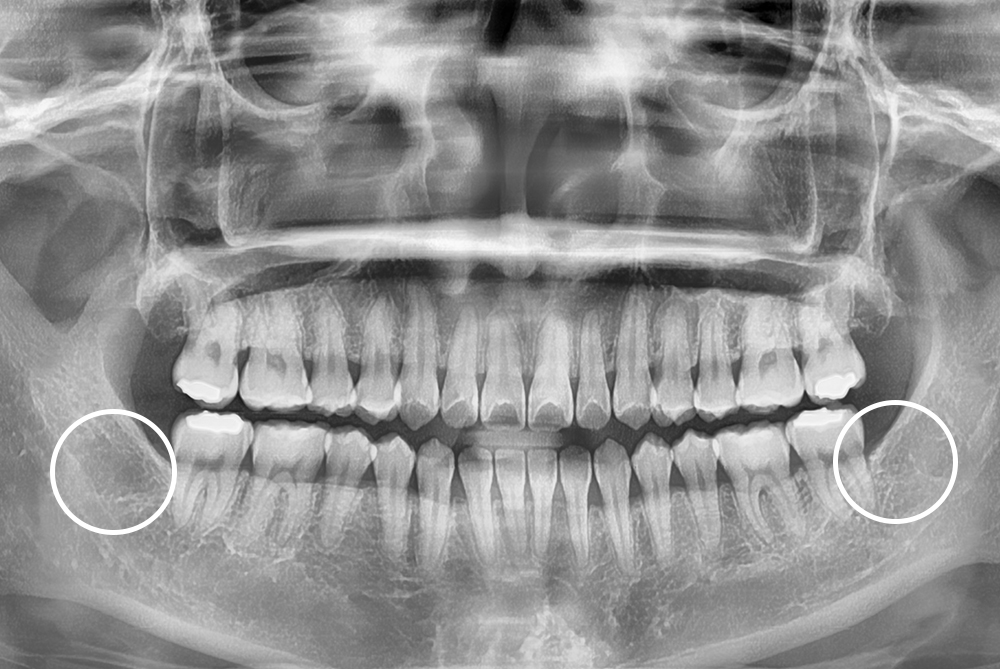

[사랑니] 매복 사랑니 발치

치료전 : 2019-03-08